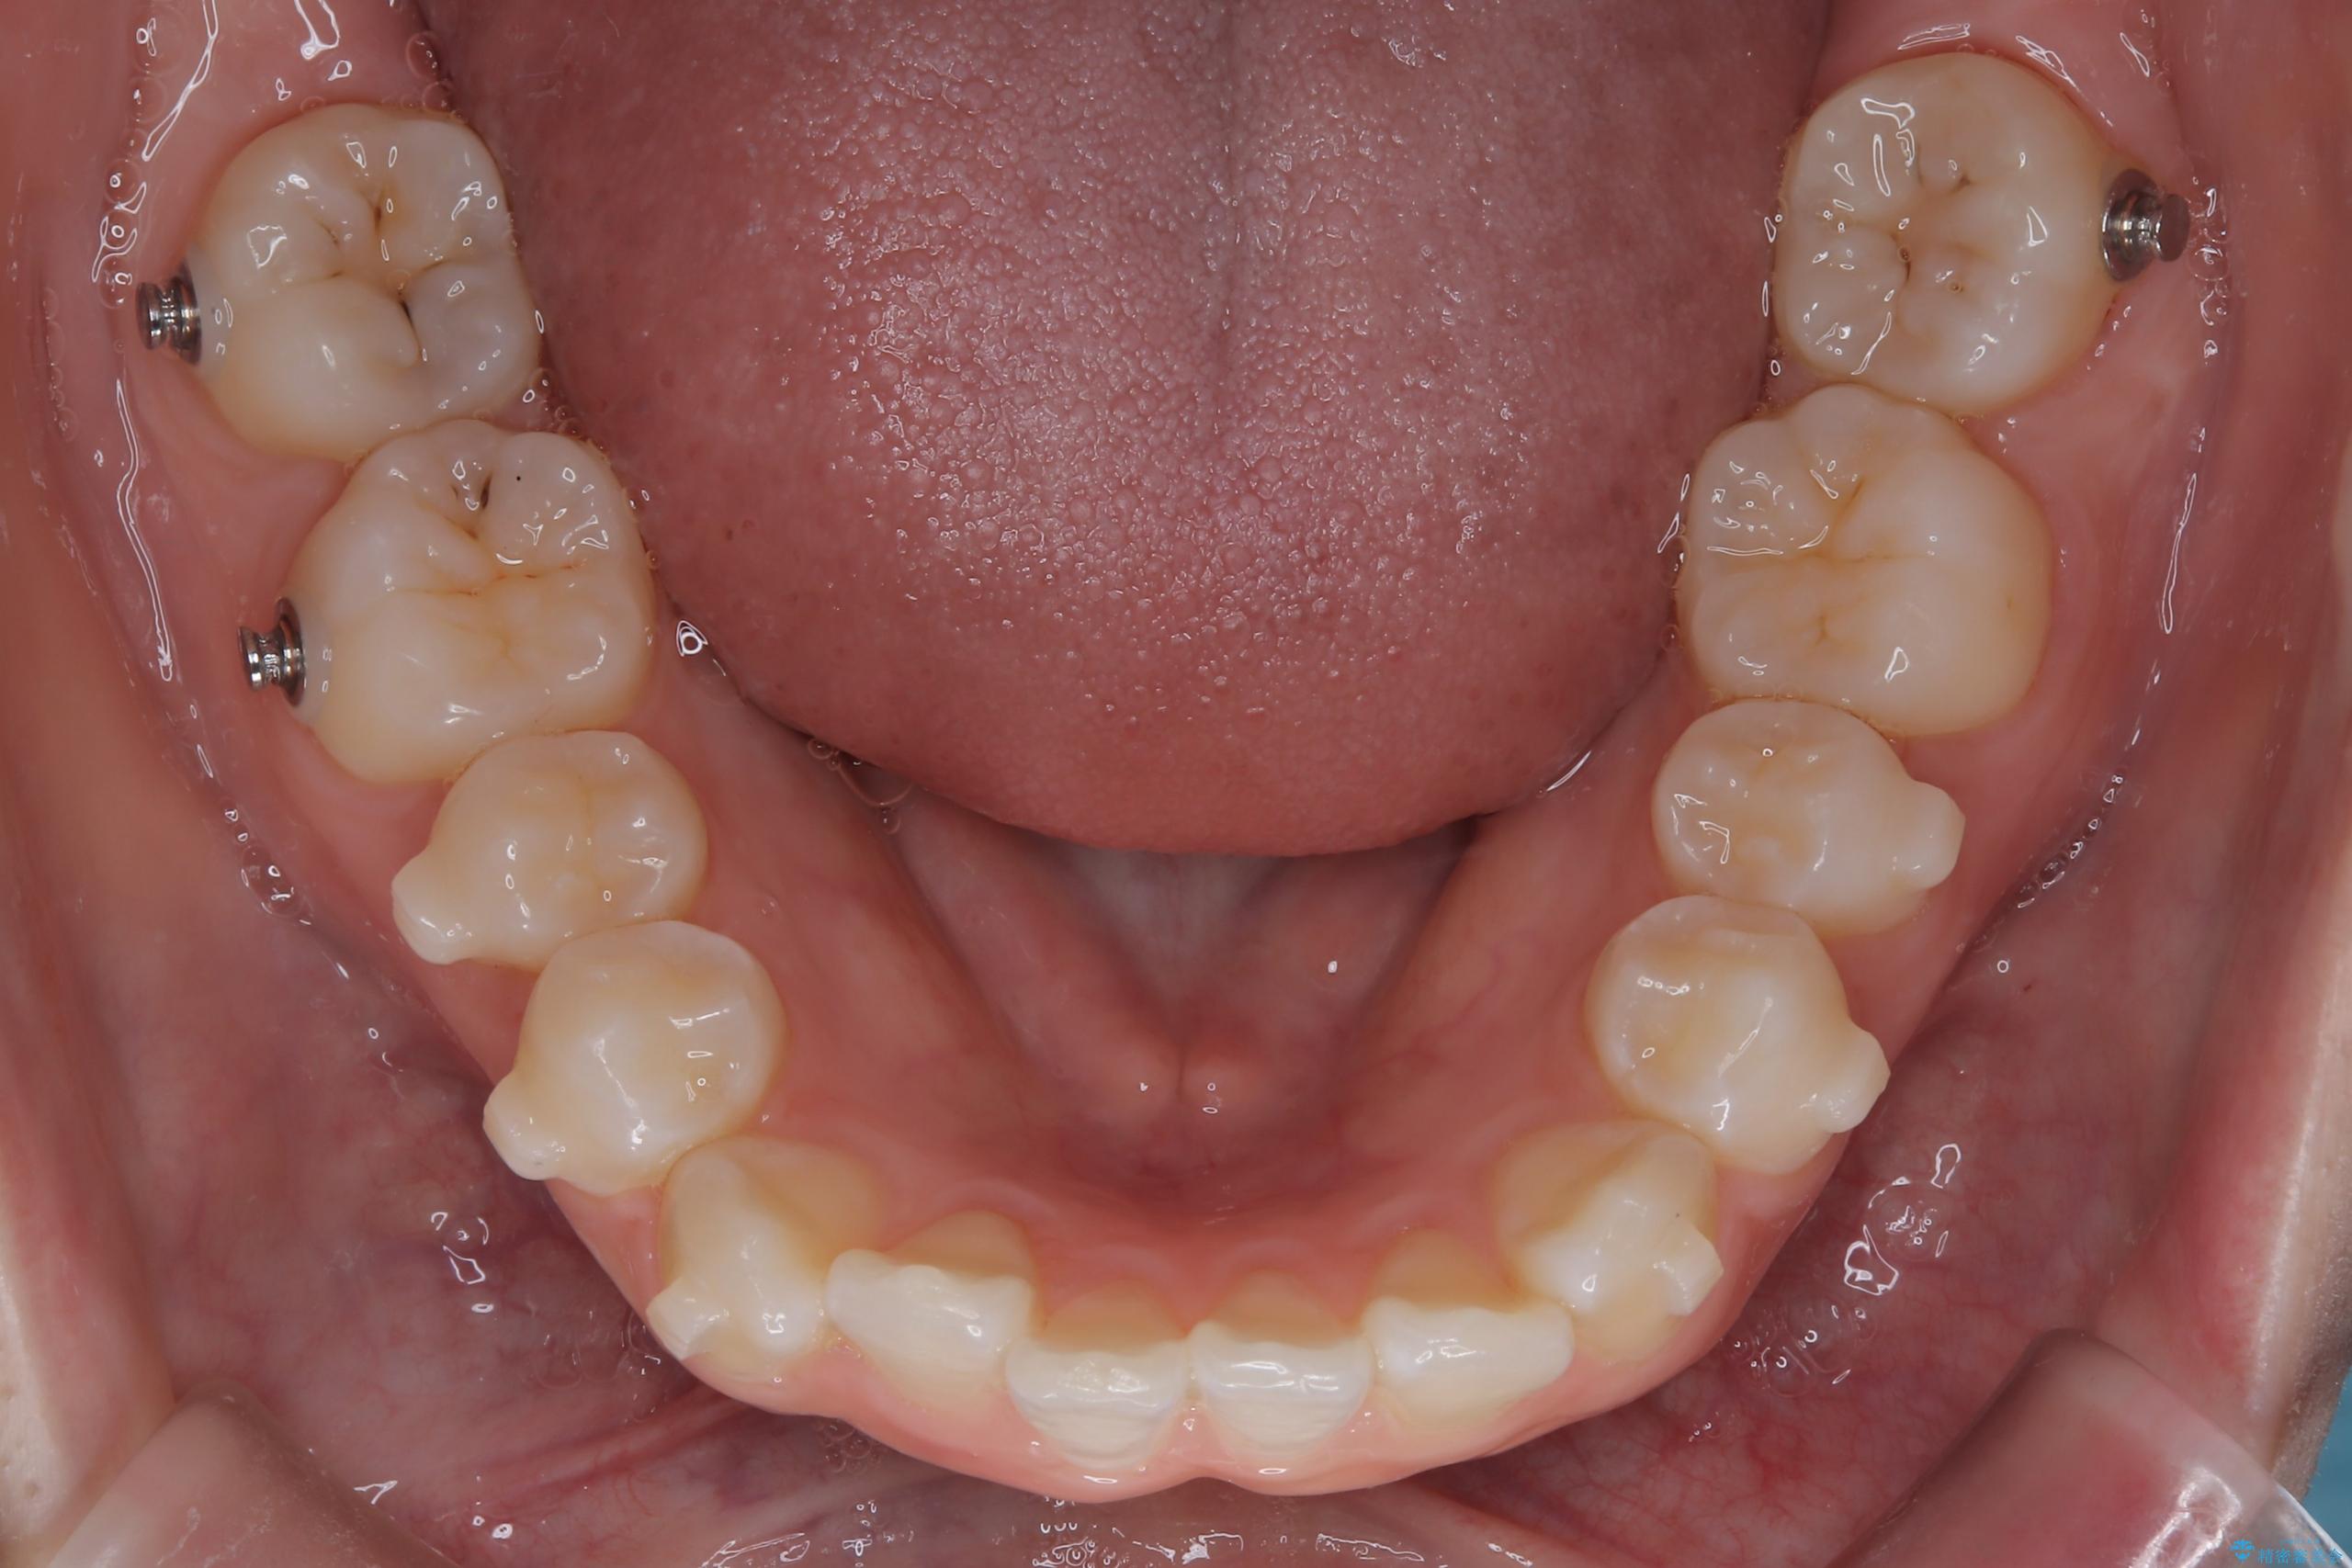

- 前歯のデコボコ(叢生)を気にされてご来院されました。精密な検査の結果、歯が並ぶスペースが不足していることが判明。患者様のご希望から、透明で目立ちにくいインビザライン(マウスピース矯正)による治療計画を立案しました。抜歯を避け、奥歯全体を奥へ動かす遠心移動という方法でスペースを確保し、前歯の叢生を解消することを目指します。

今回の矯正治療では、透明なマウスピース型の装置インビザラインを使用しました。この装置は取り外し可能で、日常生活で目立ちません。治療は、緻密に計算された計画に基づき、段階的に作製されたマウスピースを交換していくことで、奥歯から順に全体を後方へ移動させる遠心移動を実施。これにより、前歯を並べるための十分なスペースが確保され、デコボコが解消されました。抜歯することなく、機能的にも審美的にも整った美しい歯並びを獲得していただけました。